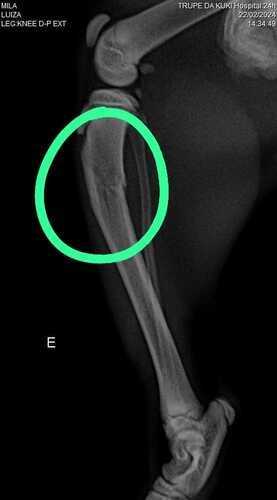

Oii pessoal, meu nome é Mila e eu tenho só 4 mesinhos. Esta noite resolvi testar se eu conseguia voar e acabei caindo do 4 andar. Mamãe quase morreu do coração, mas tá tudo bem. Tive uma fratura na minha patinha e vou precisar de uma cirurgia, infelizmente mamãe não tem como pagar tudo sozinha e eu vim pedir a ajuda de vocês. Muito obrigada 🩷